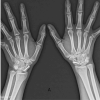

Both patients described how they reluctantly went down the waterslide with their fathers behind them at the back. Both girls apparently were trying to slow themselves down with their legs upfront. The two girls were unable to bear weight after sliding. On physical evaluation, both refused to bear weight on their left legs, and leg rolling tests was positive. Both had no other complaints. After physical clearance, the girls were X-rayed and diagnosed with hip fractures. The 10-year-old suffered a Delbet Type II fracture (Fig. 1a, b) while the 12-year-old had a Delbet Type III fracture (Fig. 2a, b). Both were admitted to the Pediatric Orthopedic Unit in our institution and were surgically treated, approximately 4 days after their initial injury, with closed reduction and internal fixation. The 10-year-old patient with the Delbet Type II fracture was fixated using NAa LCP Pediatric Hip Plate 5.0 (DePuy Synthes, Raynham, MA, USA) (Fig. 1c, d), as recommended by Beaty et al. [1]. The 12 years old patient, who suffered from the Delbet Type III fracture, was overweight for her age at roughly 65 kg. The surgeon’s intra-operative decision was to fixate her with more robust hardware, using an adult Compression Hip Screw (Smith and Nephew Richards, Memphis, TN, USA) augmented with a 7.5 mm cannulated screw to prevent rotation (Fig. 2c , d).